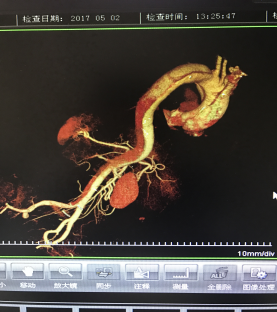

5月2號劉大伯照常早起干活,突然胸部劇烈疼痛,難以忍受,全身大汗,同時伴有右上肢發(fā)涼,他心想這次心絞痛比之前嚴(yán)重的多啊,趕緊叫上孩子到吉林國文醫(yī)院心血管內(nèi)科住院,患者長期高血壓病史,血壓一直控制不理想,大夫給他做了檢查,測左上肢血壓:82/45mmHg,右上肢血壓測不出,心率52次/分,右側(cè)肱動脈、尺動脈、橈動脈搏動消失,左側(cè)股動脈搏動較右側(cè)弱?!霸懔?,雙側(cè)血壓差別這么大,是不是主動脈夾層了?”,接診大夫趕緊找來李主任,李主任反復(fù)詢問患者病情,表情突然凝重起來,患者胸痛這么明顯,血壓低的厲害,主動脈夾層的可能性很大。二話不說,李主任立即聯(lián)系影像科的醫(yī)生準(zhǔn)備做主動脈CTA,移動患者做檢查的過程大夫們非常小心,嚴(yán)密監(jiān)測患者血壓變化情況。兩個小時后結(jié)果出來了,主動脈夾層從升主動脈一直撕裂到左側(cè)髂總動脈!??!

從開始學(xué)醫(yī)到現(xiàn)在已經(jīng)快9年了,主動脈夾層患者也見過一些,但像劉大伯這種危險類型的還是第一次見到,心里真的為他捏把汗,撕裂的主動脈隨時都有可能破裂,生命隨時可能終止,要知道主動脈夾層的死亡率非常的高,約50%的患者發(fā)病后48小時死亡,約90%的患者發(fā)病1個月內(nèi)死亡。

李主任詳細的與劉大伯的女兒交代了病情,手術(shù)是挽救生命的唯一辦法,為了劉大伯的一線生機,我們積極聯(lián)系了我省權(quán)威的心血管外科,并做了詳細的匯報,兩家醫(yī)院對此非常重視,為劉大伯開通了綠色通道,安全的把他總到上級醫(yī)院,當(dāng)天便給他進行血管置換及覆膜支架植術(shù)。他術(shù)后恢復(fù)的很好,后來劉大伯的女兒看望我們,感嘆道:沒想到國文醫(yī)院心內(nèi)科應(yīng)急能力這么高,在那么短的時間內(nèi)診斷明確,才給了我的老父親手術(shù)的機會。